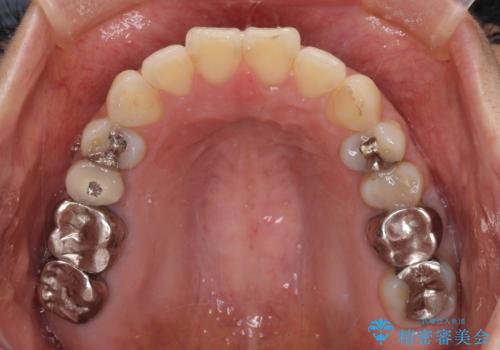

- 高校生の時に行った矯正治療の後戻りと、通院してもなかなか改善しない奥歯の痛みを気にして来院された患者様です。

左下奥歯は、前医より難治性なので抜歯も考えるよう言われたそうですが、一度もラバーダムを用いた根管治療はされていないとのことでした。

まずは左下奥歯の根管治療を行い、痛みが引いたことを確認してから矯正治療を開始しました。

後戻りは軽微であったため、インビザライン・ライトにて歯列を整えました。